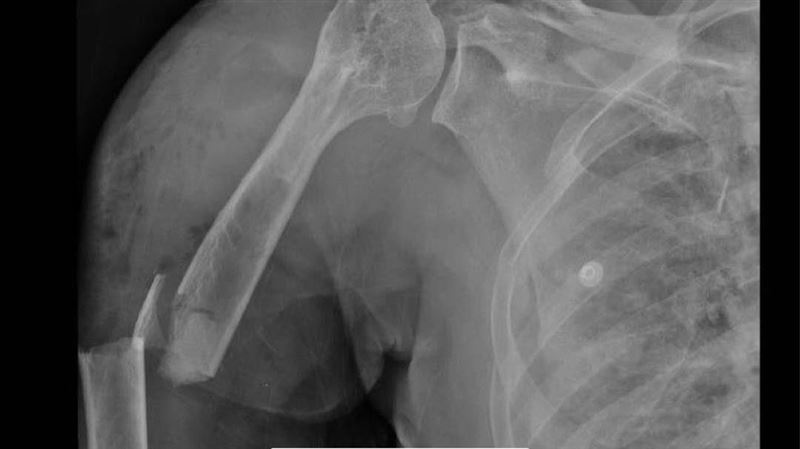

黃婦事發當天做完太空包的工作後,騎機車返家途中,遭一輛小貨車撞上,緊急被送往彰化醫院急診,全身都是傷,右上臂開放性骨折、右側血胸,右鎖骨、肱骨、橈骨、第3至5掌骨、骨盆、脛骨、腓骨,及第6至9節胸椎、胸骨、2側多處肋骨皆出現骨折。由於血壓持續下降,最低僅62/28 mmHg,因多重創傷與血胸,彰化醫院立即啟動創傷小組,並送入加護病房。

黃婦騎車返家遭小貨車撞,全身多處骨折,光是肋骨就斷了21處,傷勢相當嚴重,緊急送往彰化醫院搶救。(圖/衛福部彰化醫院提供)